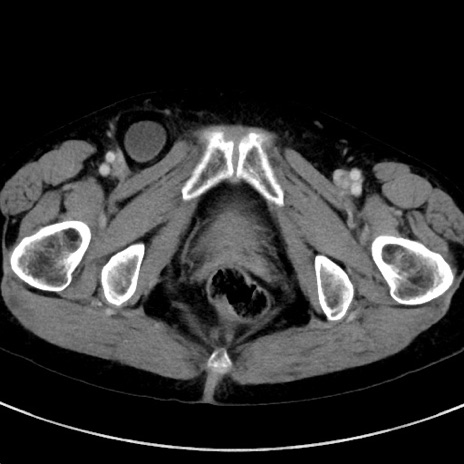

症例23(横断像)

【症例】70歳代女性

【主訴】下腹部痛・嘔吐

【現病歴】2日前より腹痛あり。昨日嘔吐あり。症状改善しないため来院。

【既往歴】胃GISTに対して胃部分切除後。

【身体所見】BT 37.1℃、BP 128/77mmHg、腹部:平坦・軟、下腹部に圧痛あり。

【データ】WBC 10200、CRP 0.31